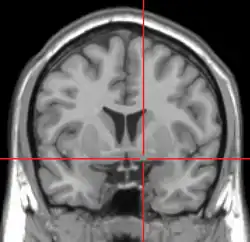

Jądro podstawne Meynerta (ang. basal nucleus of Meynert, NBM) – grupa komórek nerwowych istoty bezimiennej kresomózgowia, bocznie od guza popielatego, wysyłająca liczne projekcje do kory nowej. Stanowi część układu cholinergicznego mózgowia. Degeneracja jądra Meynerta obserwowana jest w przebiegu choroby Parkinsona, choroby Alzheimera i w otępieniu z ciałami Lewy’ego. Nazwa tej struktury anatomicznej upamiętnia Theodora Meynerta.